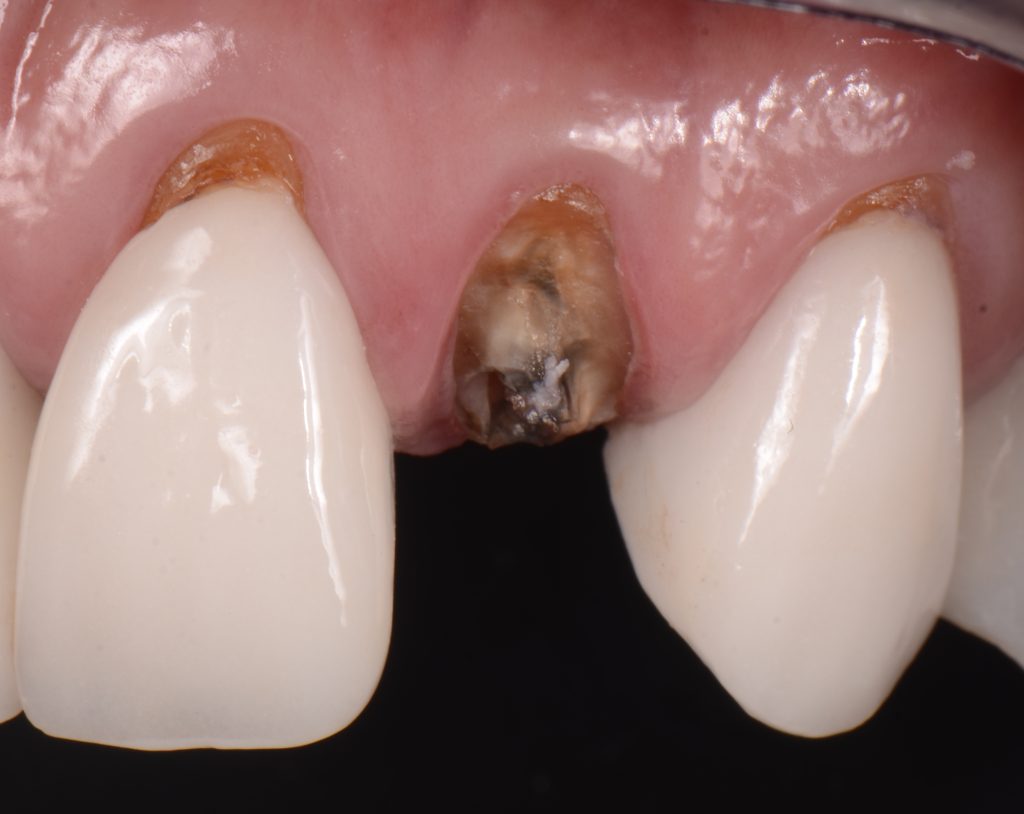

For instance, with dental crowns preliminary failure is when the luting cement seal clinically fails resulting in microleakage between the crown and the tooth (this preliminary failure is impossible to be initially detected clinically). Such microleakage will eventually cause a degradation, or washout, of the luting cement and may eventually be manifested as recurrent caries, loss of retention, fractured posts, or complete dislodgment of the crown and foundation restoration. (Figs. 3-4)

At this point the tooth or crown is most vulnerable to the heinous attack of soft bread.

This is also very common when the provisional cement on a temporary restoration is washed out, and suddenly, a soft, normally sticky bread will simply facilitate the dislodgement of the restoration.